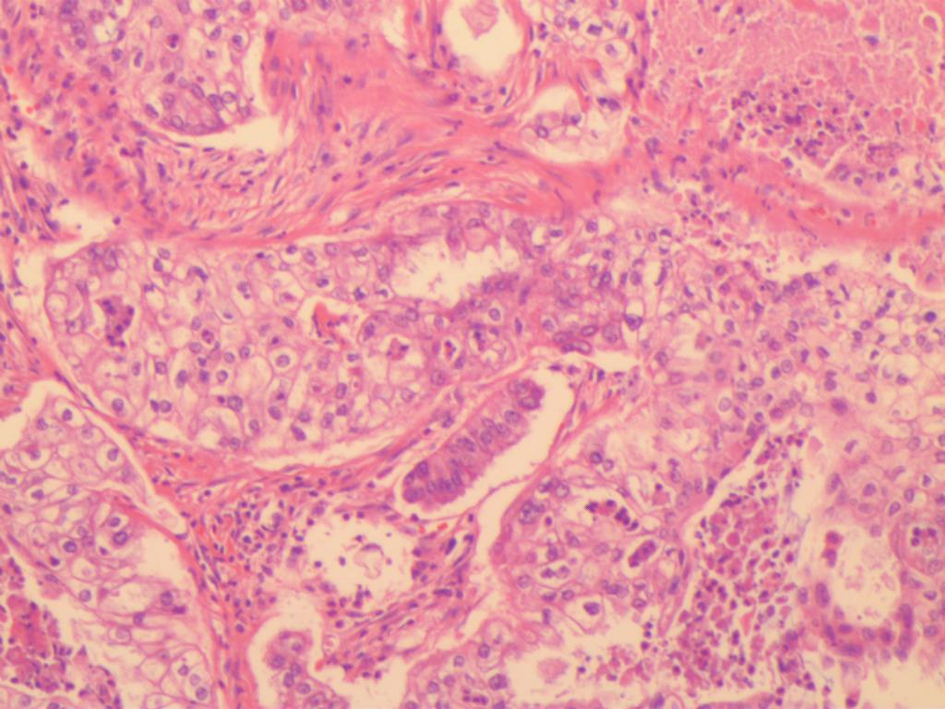

Primary clear cell carcinoma of the gallbladder: A case report

LIU TT, FU X, WANG YM, et al. Clinicopathologic observation of rare gallbladder malignant clear cell tumors[J]. Mod Oncol, 2019, 27(9): 1566-1570. DOI: 10.3969/j.issn.1672-4992.2019.09.024.

刘坦坦, 付欣, 王映梅, 等. 胆囊罕见恶性透明细胞肿瘤的临床病理观察[J]. 现代肿瘤医学, 2019, 27(9): 1566-1570. DOI: 10.3969/j.issn.1672-4992.2019.09.024.